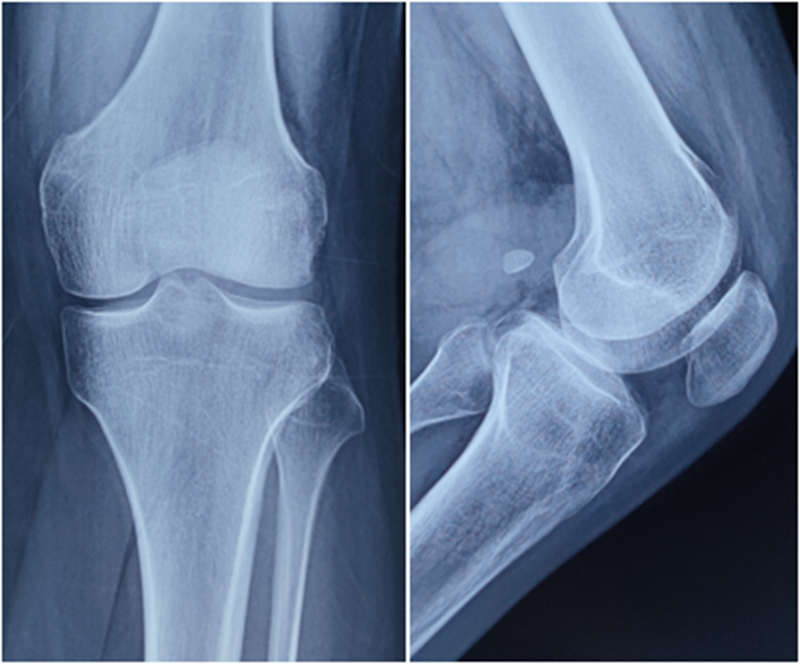

典型病例,张X,男,18岁,因扭伤致左膝关节疼痛伴活动受限1月余入院。

诊断:1.左膝前交叉韧带损伤;2.左膝外侧半月板损伤合并囊肿。

手术方案:左膝关节镜下清理、滑膜切除、外侧半月板部分切除成形、前交叉韧带重建术。

术前X线

术后X线